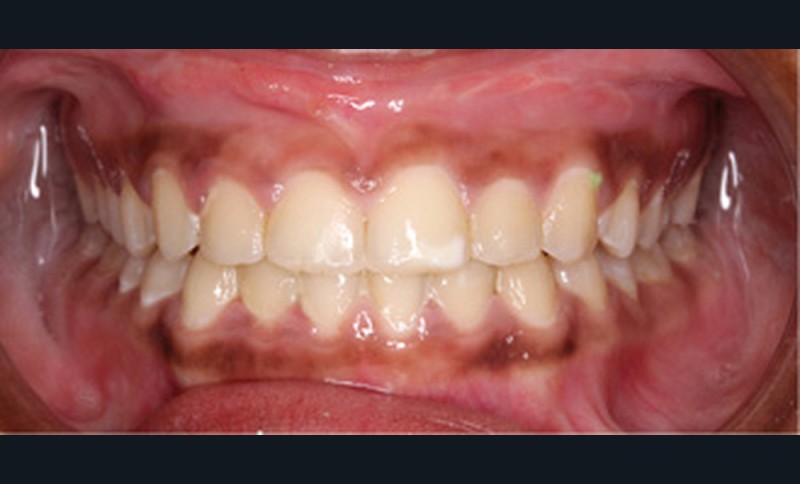

Examen clinique (fig. 1a-h)

À l’examen de face, Anisa présente un visage ovalaire, des hémifaces symétriques, des lignes horizontales parallèles, une augmentation de l’étage inférieur, une occlusion labiale légèrement forcée et des dents mandibulaires exposées au sourire. Les profils général et sous-nasal sont concaves avec un angle naso-labial augmenté et une prochéilie inférieure.

L’examen clinique endo-buccal révèle une denture adulte jeune avec un inversé d’articulé antérieur de 13 à 23, des tatouages gingivaux ethniques et des taches de décalcifications, un parodonte sain mais un brossage insuffisant.

L’arcade maxillaire est en V et la voûte palatine profonde. L’arcade mandibulaire a une forme en U (non-concordance des formes d’arcade) et présente des malpositions des dents cuspidées. La médiane mandibulaire est décalée à gauche de 2 mm ; le recouvrement antérieur est de 2 mm ; les molaires sont en classe III avec un surplomb inversé.